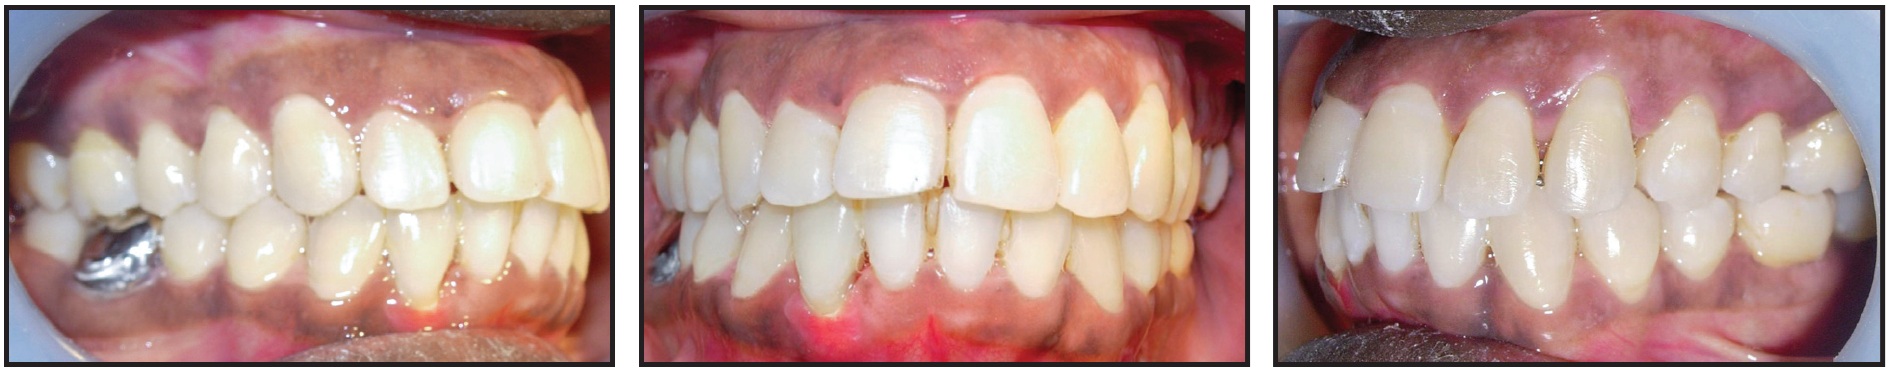

Fig. 3 Patient after five months of treatment, showing relief of traumatic occlusion and improved alignment.

Six months later, a three-month phase of orthodontic finishing was carried out to close the residual spaces in the lower arch. A continuous elastomeric chain was placed from the lower right second molar to the lower left first molar, initially bypassing the right lateral incisor to minimize the forces on this tooth. After correction of the anterior crossbite and closure of residual spaces, the bite planes and fixed appliances were removed (Fig. 7). A normal overbite of about 2mm ensured stability of the anterior crossbite correction.

Fig. 7 After three months of orthodontic finishing, following six months of periodontal treatment and healing.

During a total 14 months of treatment, the metal crown on the lower right first molar collapsed due to the heavier occlusal forces from the bite plane on the opposing upper molar. A new metal crown was placed at the end of treatment (Fig. 8).

Fig. 8 Patient after 14 months of treatment.